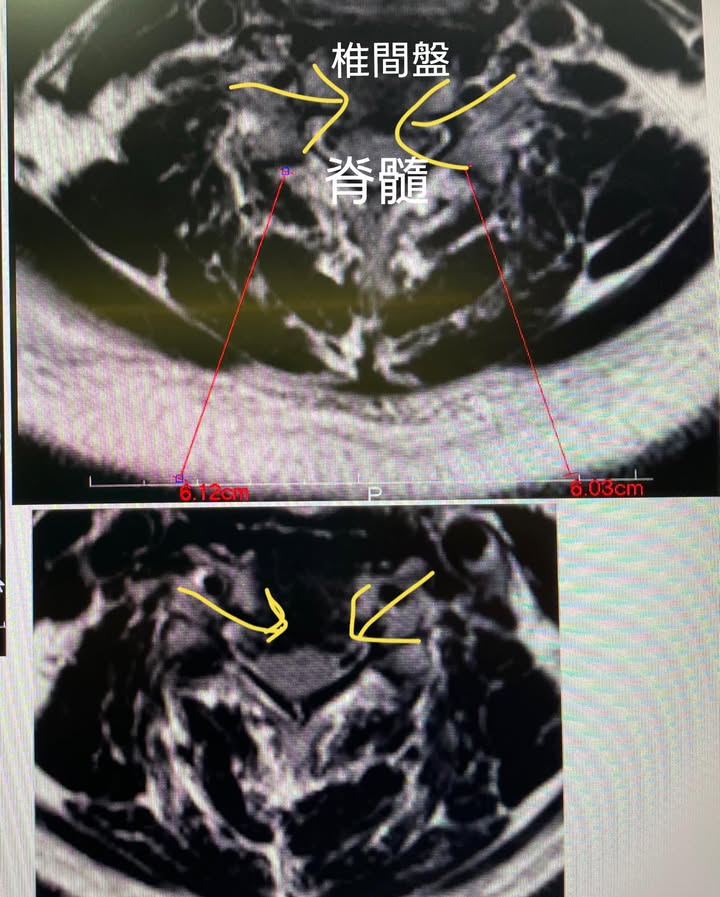

#脊髓型頸椎病壓迫

1.根據北美脊髓外科協會建議,出現MRI有明顯水腫變性患者,應高度考慮手術,但最終一切以患者臨床症狀為主,手術方法為ACDF,即椎間盤切除術就是把椎間盤切除。醫生會由頸部前面進入,通過喉部抵達破損的椎間盤。把頸部肌肉、氣管和食道撥開,就能接觸椎間盤和脊椎骨,切除椎間盤後,在兩脊椎骨之間會有空隙,為防止脊椎骨塌下及互相摩擦,一般會利用移植骨或代替品填滿該位置。移植骨成為兩個脊椎骨之間的橋樑,以進行脊椎融合。移植骨和脊椎骨通常會以金屬板及骨釘固定在一起而不能調動。手術後身體會開始自然癒合,新的細胞也於移植骨周圍形成。三至六個月後,移植骨會與上下的脊椎骨融合成一塊堅實的骨頭 。在儀器及融合術運作下,骨頭有機會沿著金屬板及骨釘生長 – 類似鋼筋混凝土般 。

✳️治療:9/15~12/246,總共治療十八次,症狀改善超過八成。

長期保守治療無效者,且經 CT 或MRI檢查明確診斷,或出現大小便失禁,跟肌肉萎縮患者應接受手術治療。